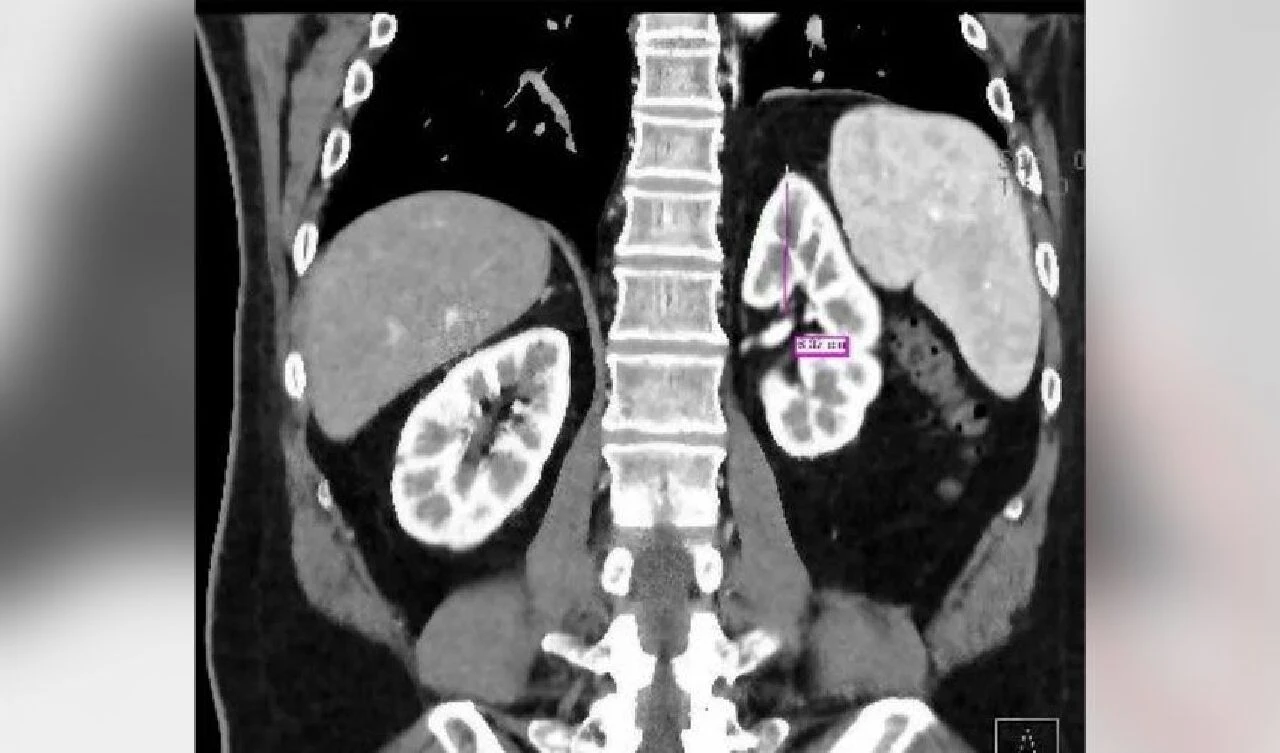

''Hatırladığım bir sonraki şey, burnumda tüpler olan bir hastane yatağında olduğum ve bilincimin gidip geldiğiydi. Yan tarafımdaki bandajın altından kanlı bir sıvı akan bir tüp vardı."